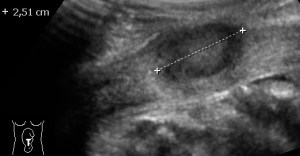

Multiple Myomas in pregnancy 2